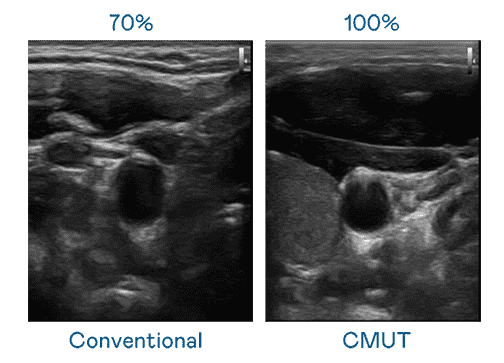

CMUT 技术是一种用电容式微机电元件来产生超音波讯号的技术。。。与传统 PZT 压电式技术相比,,CMUT 频宽增加 30%,,,,更宽频的超音波讯号让影像解析度大幅提升,,,是实现高影像品质医疗超音波扫描、、、促进精准医疗发展的关键技术。。。。

超音波影像的解析度高低,,,,首先取决于探头能发出的讯号频宽。。森林舞会 CMUT 可提供高清晰的超音波讯号,,,提供高频宽、、高灵敏度、、、、影像纹理细节更高的超音波影像,,协助医护人员缩短影像判读时间及利用精准的医疗影像进行诊断。。。